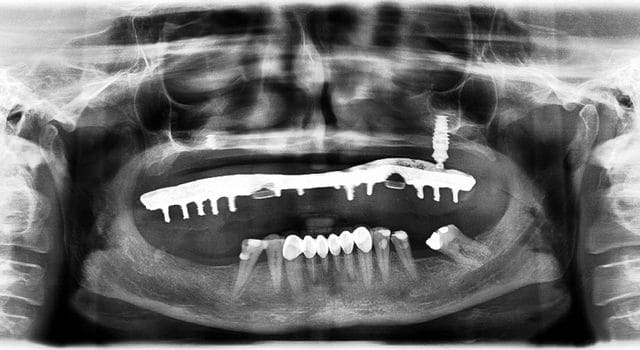

Voici donc les panos pour vos petits yeux ébahis

Profitez bien : elles sont ds l ordre chronologique...

Je vous donne une petite info : le comblement au BioOss a échoué largement...et on lui propose des greffes crâniennes à présent

- On y voit un manque flagrant de densité du greffon

- On y voit une perte d'un implant sans changement de plan de traitement, on se retrouve avec un seul implant du coté où mastique le patient

- On y voit une armature qui baille sur le seul implant qui reste secteur 2, et donc manque de passivité

- On y voit ce qui devait arriver,

Mais je vois aucun rapport entre l’échec et la nature du matériau mis en place dans le sinus....